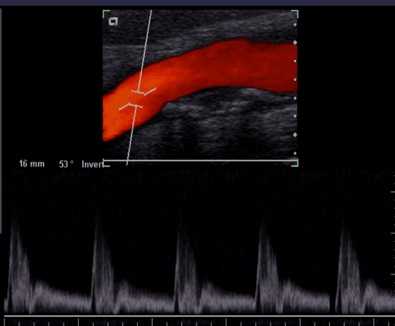

频谱多普勒显示

彩超是彩色多普勒超声的简称。它是根据多普勒效应在二维超声显像(即B超)的基础上,叠加彩色血流信号,实现彩色血流显像的一种方法。